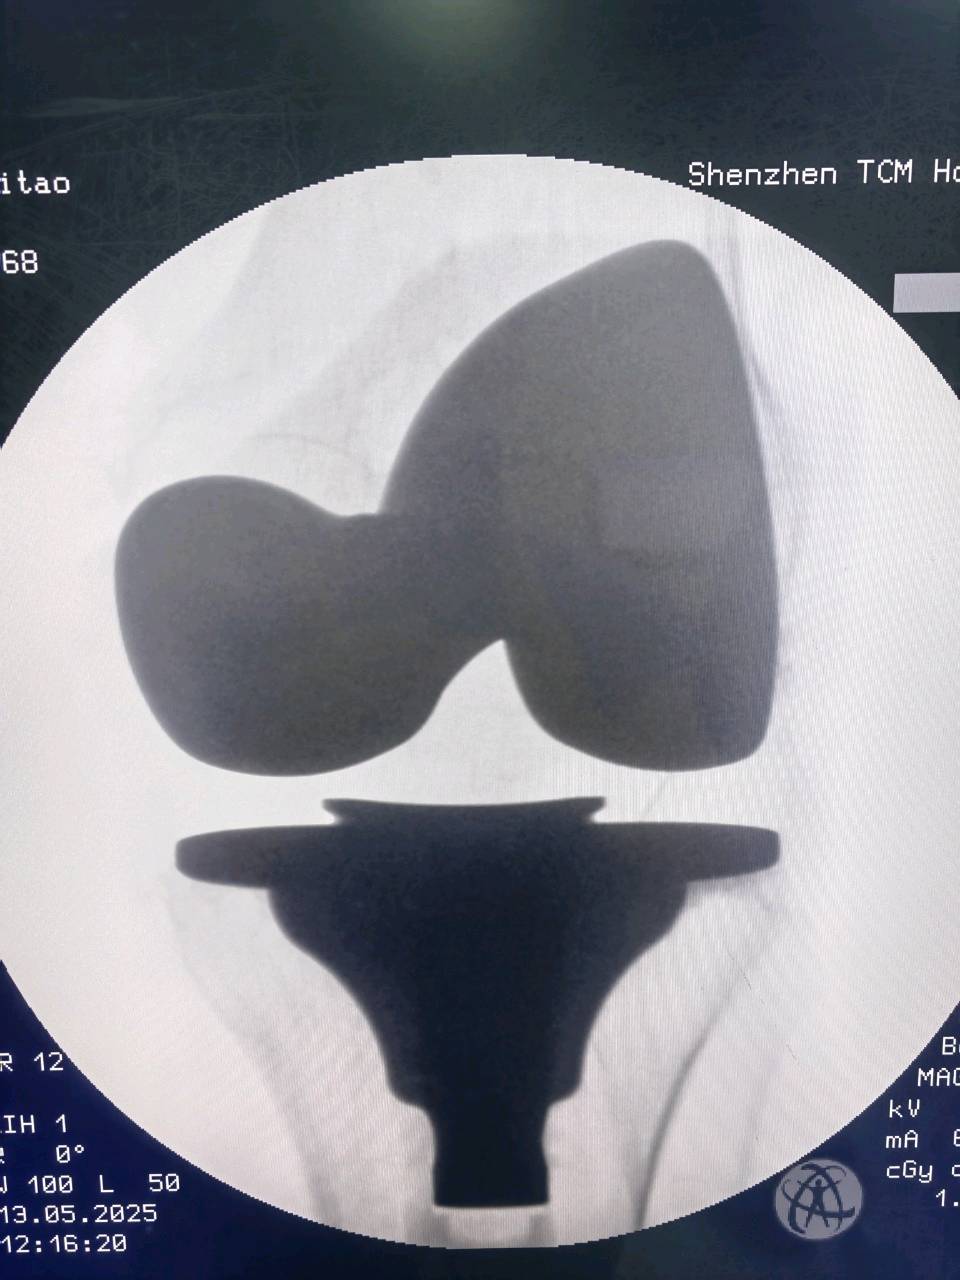

· 假体材料: 目前主流的假体是“钴铬钼合金”对“超高交联聚乙烯”。这种组合具有极佳的耐磨性,大大延长了假体的使用寿命。

· 精准医疗: 基于患者解剖结构的“个性化截骨工具”和“机器人辅助手术”正在推广应用,让手术更加精准,效果更可预测。